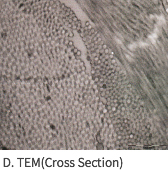

SEM Image (These have kept the collagen structure after the E-Beam sterilization.)

MEGA DERM™ PLUS 3-dimensional structure of the dermis

The world's first 'E-Beam' sterilization that does not destroy the collagen structure